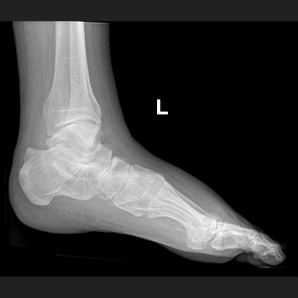

MobileSparkler移动DR是宝润的经典款产品,专为连续高强度检查而设计,始终能为医生带来清晰良好的图像。已在全球上千家医院装机,以其稳定的性能和可靠的质量成为许多医院的首选;由于其卓越的功能,可广泛应用于放射科、骨科体检科、急诊室、重症监护室、手术室和新生儿科。

配备高频高压发生器,高压输出稳定,满足多种体位需求,为清晰的临床图像提供保障。